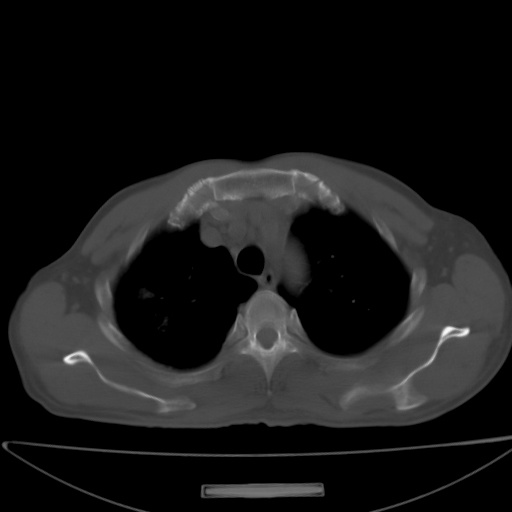

以下是引用jsgdoctor在2008-11-6 22:12:00的发言:[br]右主支气管壁明显增厚,管腔狭窄.考虑为右侧中央型肺癌伴阻塞性炎症\\肺脓肿.

以下是引用zjzjr在2008-11-6 20:25:00的发言:[br]中心型肺ca,合并阻塞性肺炎

以下是引用zsl6918在2008-11-6 19:43:00的发言:[br]右侧中心性肺癌(鳞癌)